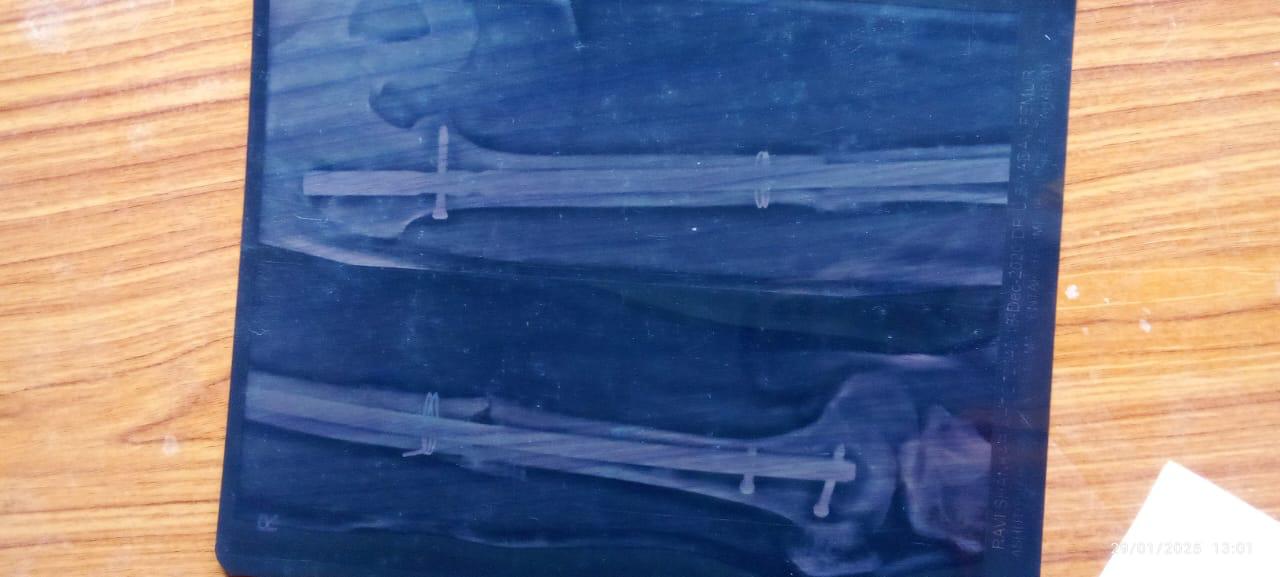

Help Ravi Shankar Stand Again: Support His Medical Recovery & Family’s Future

Ravi Shankar, the backbone of his family, is facing a life-altering challenge after a severe leg injury. He is in urgent need of financial assistance to cover medical expenses, including surgery, rehabilitation, and ongoing treatment. His family, dependent on his earnings, is struggling to meet daily needs. With your generous support, we can help Ravi regain mobility, stand on his feet again, and ensure his family doesn’t suffer. Every contribution, big or small, will bring him closer to recovery and give his loved ones hope for a better tomorrow. Let’s unite and make a difference in his life.